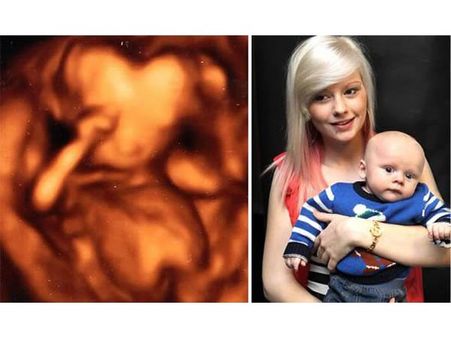

The Boy Whose Heart-Shaped Head Was Spotted In An Ultrasound

This unique-looking ultrasound image of this little boy worried the mum a lot. It was a 3D image, which made the baby look like that. Five months later, when the baby was born, he was all fine.